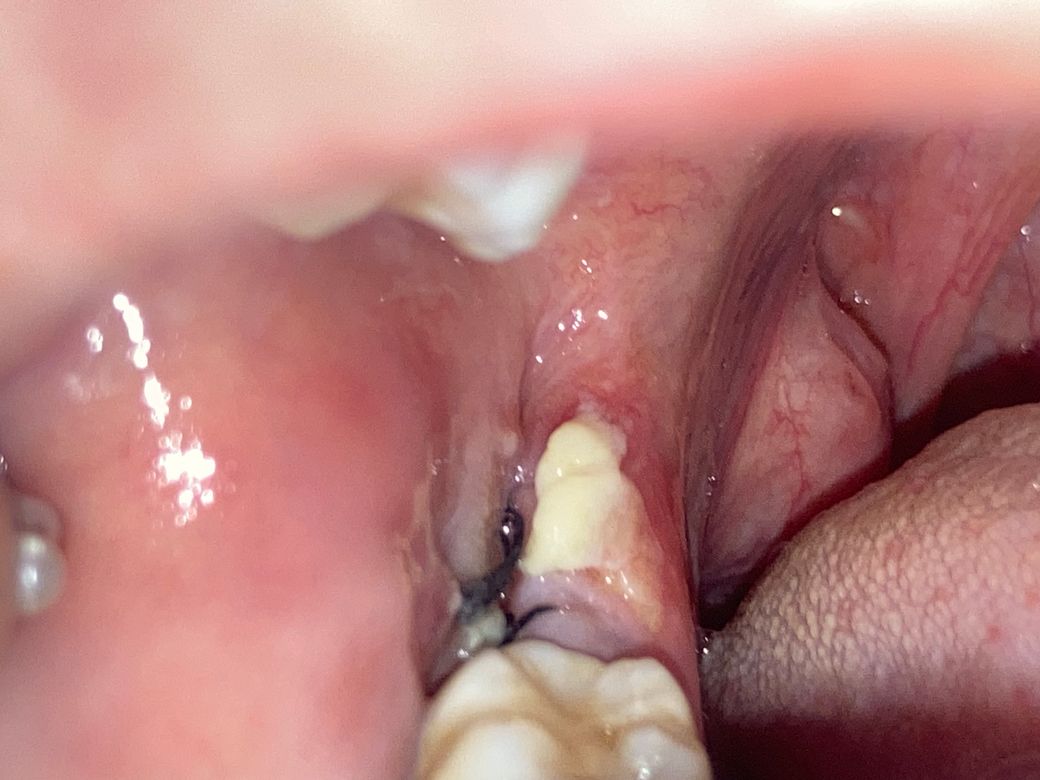

사랑니 발치 3일차 하얀덩어리의 존재?

이게 뭔지 알 수 있을까요 ㅜㅜ 위아래 동시에 뽑앗는데 아래에만 생겼어요 혹시 몰라서 제거 안했고 가글 열심히 했어요 약도 잘 챙겨먹구요 ㅜㅜ 다른 아빨 뺏을때는 이러지 않았어요

• 1번 째 사진